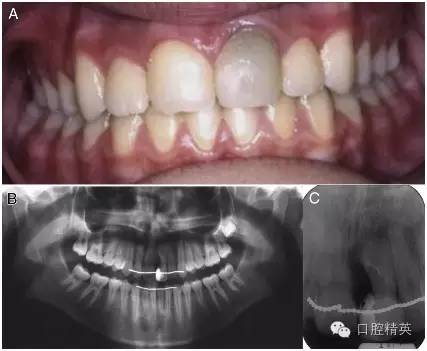

圖 4 十年后復(fù)查發(fā)現(xiàn),患牙依然保存了牙髓活力,并且全口牙齒前后牙咬合關(guān)系正常,復(fù)合樹脂修復(fù)的效果也令人滿意。(A)口內(nèi)正面像。(B)x 線全景片。(C)根尖片。

做過手術(shù) 10 年之后,患牙剩余部分保存完好。通過問診、牙髓活力測(cè)試和 x 線根尖片,患牙的牙髓活力最終被確診為正常。此外,復(fù)合樹脂修復(fù)體也是完整的,而且通過口內(nèi)臨床檢查和 x 線片檢查,未發(fā)現(xiàn)有患牙有繼發(fā)齲的跡象。因?yàn)樵瓉淼臉渲迯?fù)材料已經(jīng)變色,患者被建議重新做一下此牙的修復(fù)(圖 4)。